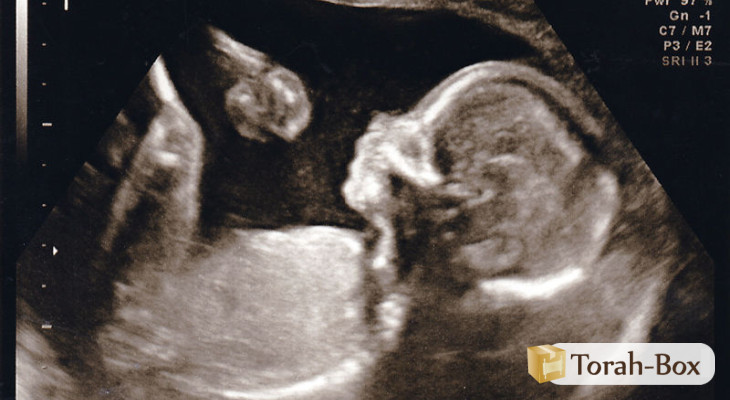

Je suis arrivée à l'hôpital. La femme médecin m'a demandé pourquoi je consultais, et je lui ai raconté tout ce qui m'arrivait. Elle a lu tous les documents médicaux et a décidé de me refaire un examen interne et de voir ce que ça donnerait (d'après ce qu'avaient écrit les deux autres médecins, seul un examen interne pouvait donner des éléments). Pendant l'examen, elle m'a dit que le fœtus avait grandi et qu'il fallait faire un examen externe.

"Vous êtes sûre ?" lui ai-je demandé. Elle a répondu que oui. Elle a étalé le gel, a posé le moniteur sur moi et a commencé à balayer mon ventre. Et la tête a apparu, le dos, les mains, les pieds, et le cœur qui battait ! Un enfant normal et en bonne santé !

Je me suis mise à trembler, je ne croyais pas ce que je voyais et entendais. J'ai bien failli m'évanouir. Elle a alors tenté de me calmer afin de pouvoir entendre le battement du cœur de façon limpide. "J'allais avorter demain, sur les ordres du médecin…" dis-je à la femme médecin, ébahie. "C'est un miracle" dit-elle. Nous avons toutes les deux pleuré. Quelle chance d'avoir pu parler avec ce Rav qui ne m'a pas abandonnée. Ce n'est pas pour rien que l'on dit que les paroles d'un Rav sont celles de D.ieu vivant.